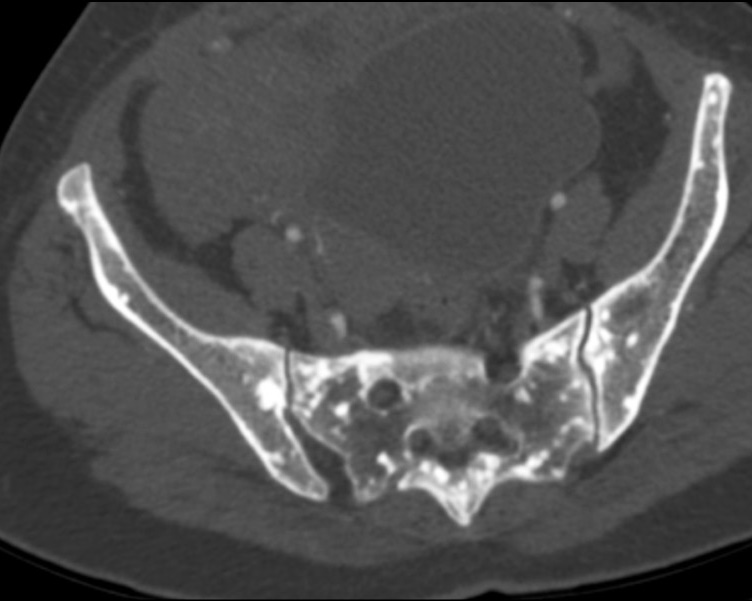

Остеопойкилия ― редкая форма наследственной доброкачественной дисплазии костей, случайно обнаруживаемая при рентгенографии. Характеризуется специфической рентгенологической картиной ― диффузными склеротическими участками кости круглой или овальной симметричной формы, определяемыми по всему скелету. Правильная постановка диагноза очень важна, поскольку поражения такого типа схожи с костными метастазами.

В данной статье представлен случай остеопойкилии у пациентки, обратившейся в нашу клинику с жалобой на кратковременную потерю сознания без признаков онемения, покалывания, слабости в ногах или других частях тела. Компьютерная томография показала множественные мелкие склеротические очаги, рассеянные по грудному и поясничному отделу позвоночника, рёбрам, тазовым костям, крестцу и проксимальному отделу бедренных костей с обеих сторон. При остеосцинтиграфии всего тела с применением технеция-99м повышения накопления препарата не выявлено. У пациентки были диагностированы характерные рентгенологические признаки остеопойкилии, после чего она находилась под наблюдением.